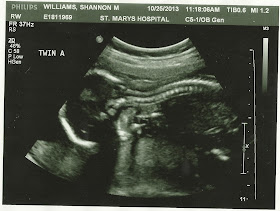

20 weeks (and 6 days), and it's still hard to believe that we are going to have two babies. My belly is expanding, my back hurts more, and I'm still in bed by about 9:00 every night, yet I can forget I'm even pregnant sometimes. Although A and B don't seem to have any problem giving my belly some not-so-gentle reminder kicks every so often (like whoever is kicking me in the belly button right now...you could totally stop doing that).  I can feel their kicks getting stronger (not like two weeks ago when "was that a baby...or just my stomach?" was the norm). Tyson can even feel them, and sometimes they're so strong they startle me.

I thought that maybe getting to see them again last week would make it more believable. While it was fun, and they were moving around like crazy, it's still weird to think that there are TWO LITTLE PEOPLE INSIDE OF ME.

A is the stubborn one (I'm convinced it's a feisty little girl, Tyson thinks it's a boy), and while he/she was moving around like crazy, they just wouldn't turn around so we could get a good angle to see his/her face.  He/she really liked showing off their spine though...

B was much more photogenic, and started with this feet-above-the-head maneuver just to show off after how stubborn A was being. Then he/she decided to go for the ultimate in cuteness and start sucking his/her thumb.